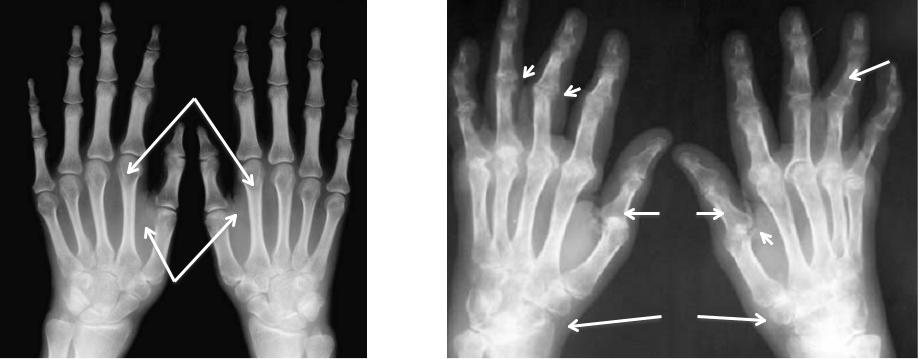

Рентгенологические изменения суставов кистей при РА

А

Б

3

А. I рентгенологическая стадия:

1– околосуставной остеопороз 2 – отек мягких тканей

Б. IV рентгенологическая стадия

1– Эрозии суставных поверхностей

2 – подвывихи в пястнофаланговых и межфаланговых суставах

3 – анкилоз костей запястья